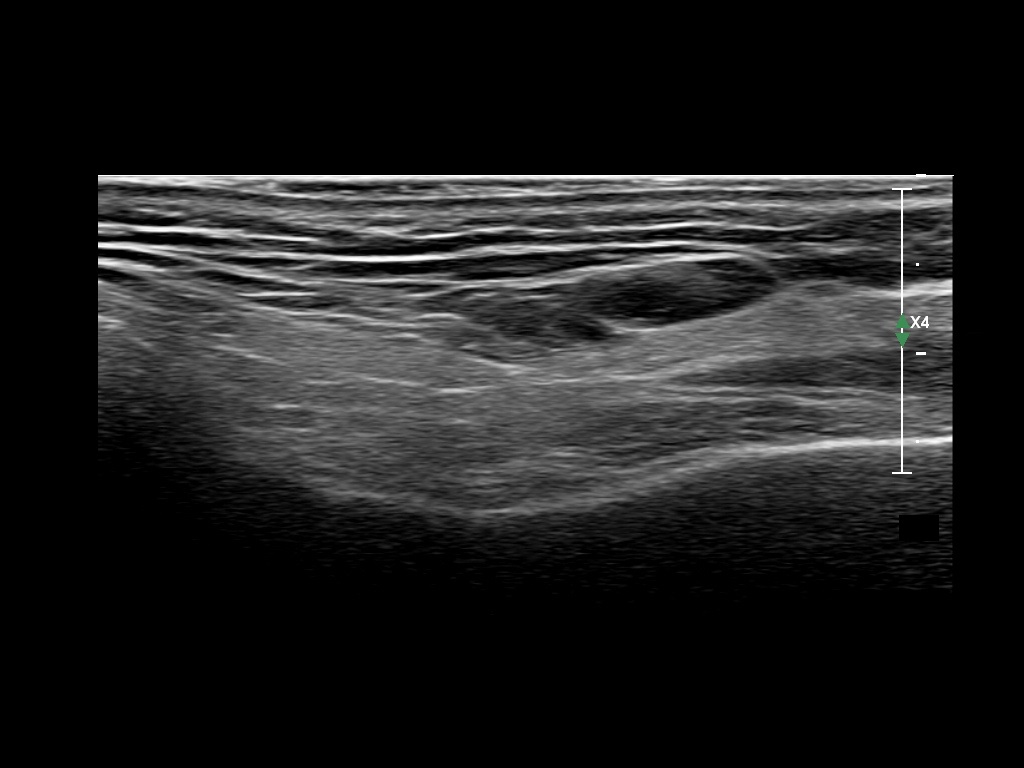

Study the first image to recognize the different layers. If you are sure about the layers, swipe to the second image to view the answer (if applicable).

Hover over an image to view the secondary image or click on the image title for more information.